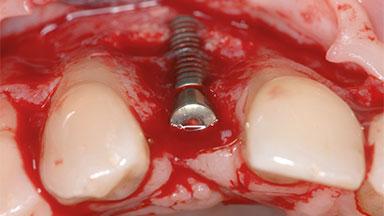

Removal of a Malpositioned Implant and Direct New Implant Placement with Simultaneous Contour Augmentation using GBR

A 35-year old female patient was referred to the Department of Oral Surgery and Stomatology at the University of Bern, Switzerland, for examination of an implant site that had exhibited clinical signs of slightly delayed wound healing. In addition, the referring clinician found no evidence for a facial bone wall when she raised a flap to gain access to the implant for abutment connection. Four months earlier, she had inserted a bone-level implant in a single-tooth gap, where the lateral incisor had been extracted due to a chronic periapical lesion on the mesial aspect of the root. Implant placement was combined with simultaneous bone augmentation using deproteinized bovine bone mineral (DBBM, Bio-Oss®; Geistlich, Wolhusen, Switzerland) and a collagen membrane (Bio- Gide®; Geistlich), followed by primary wound closure. The patient also provided the postsurgical radiograph that displayed the implant with a 3.5-mm healing cap.